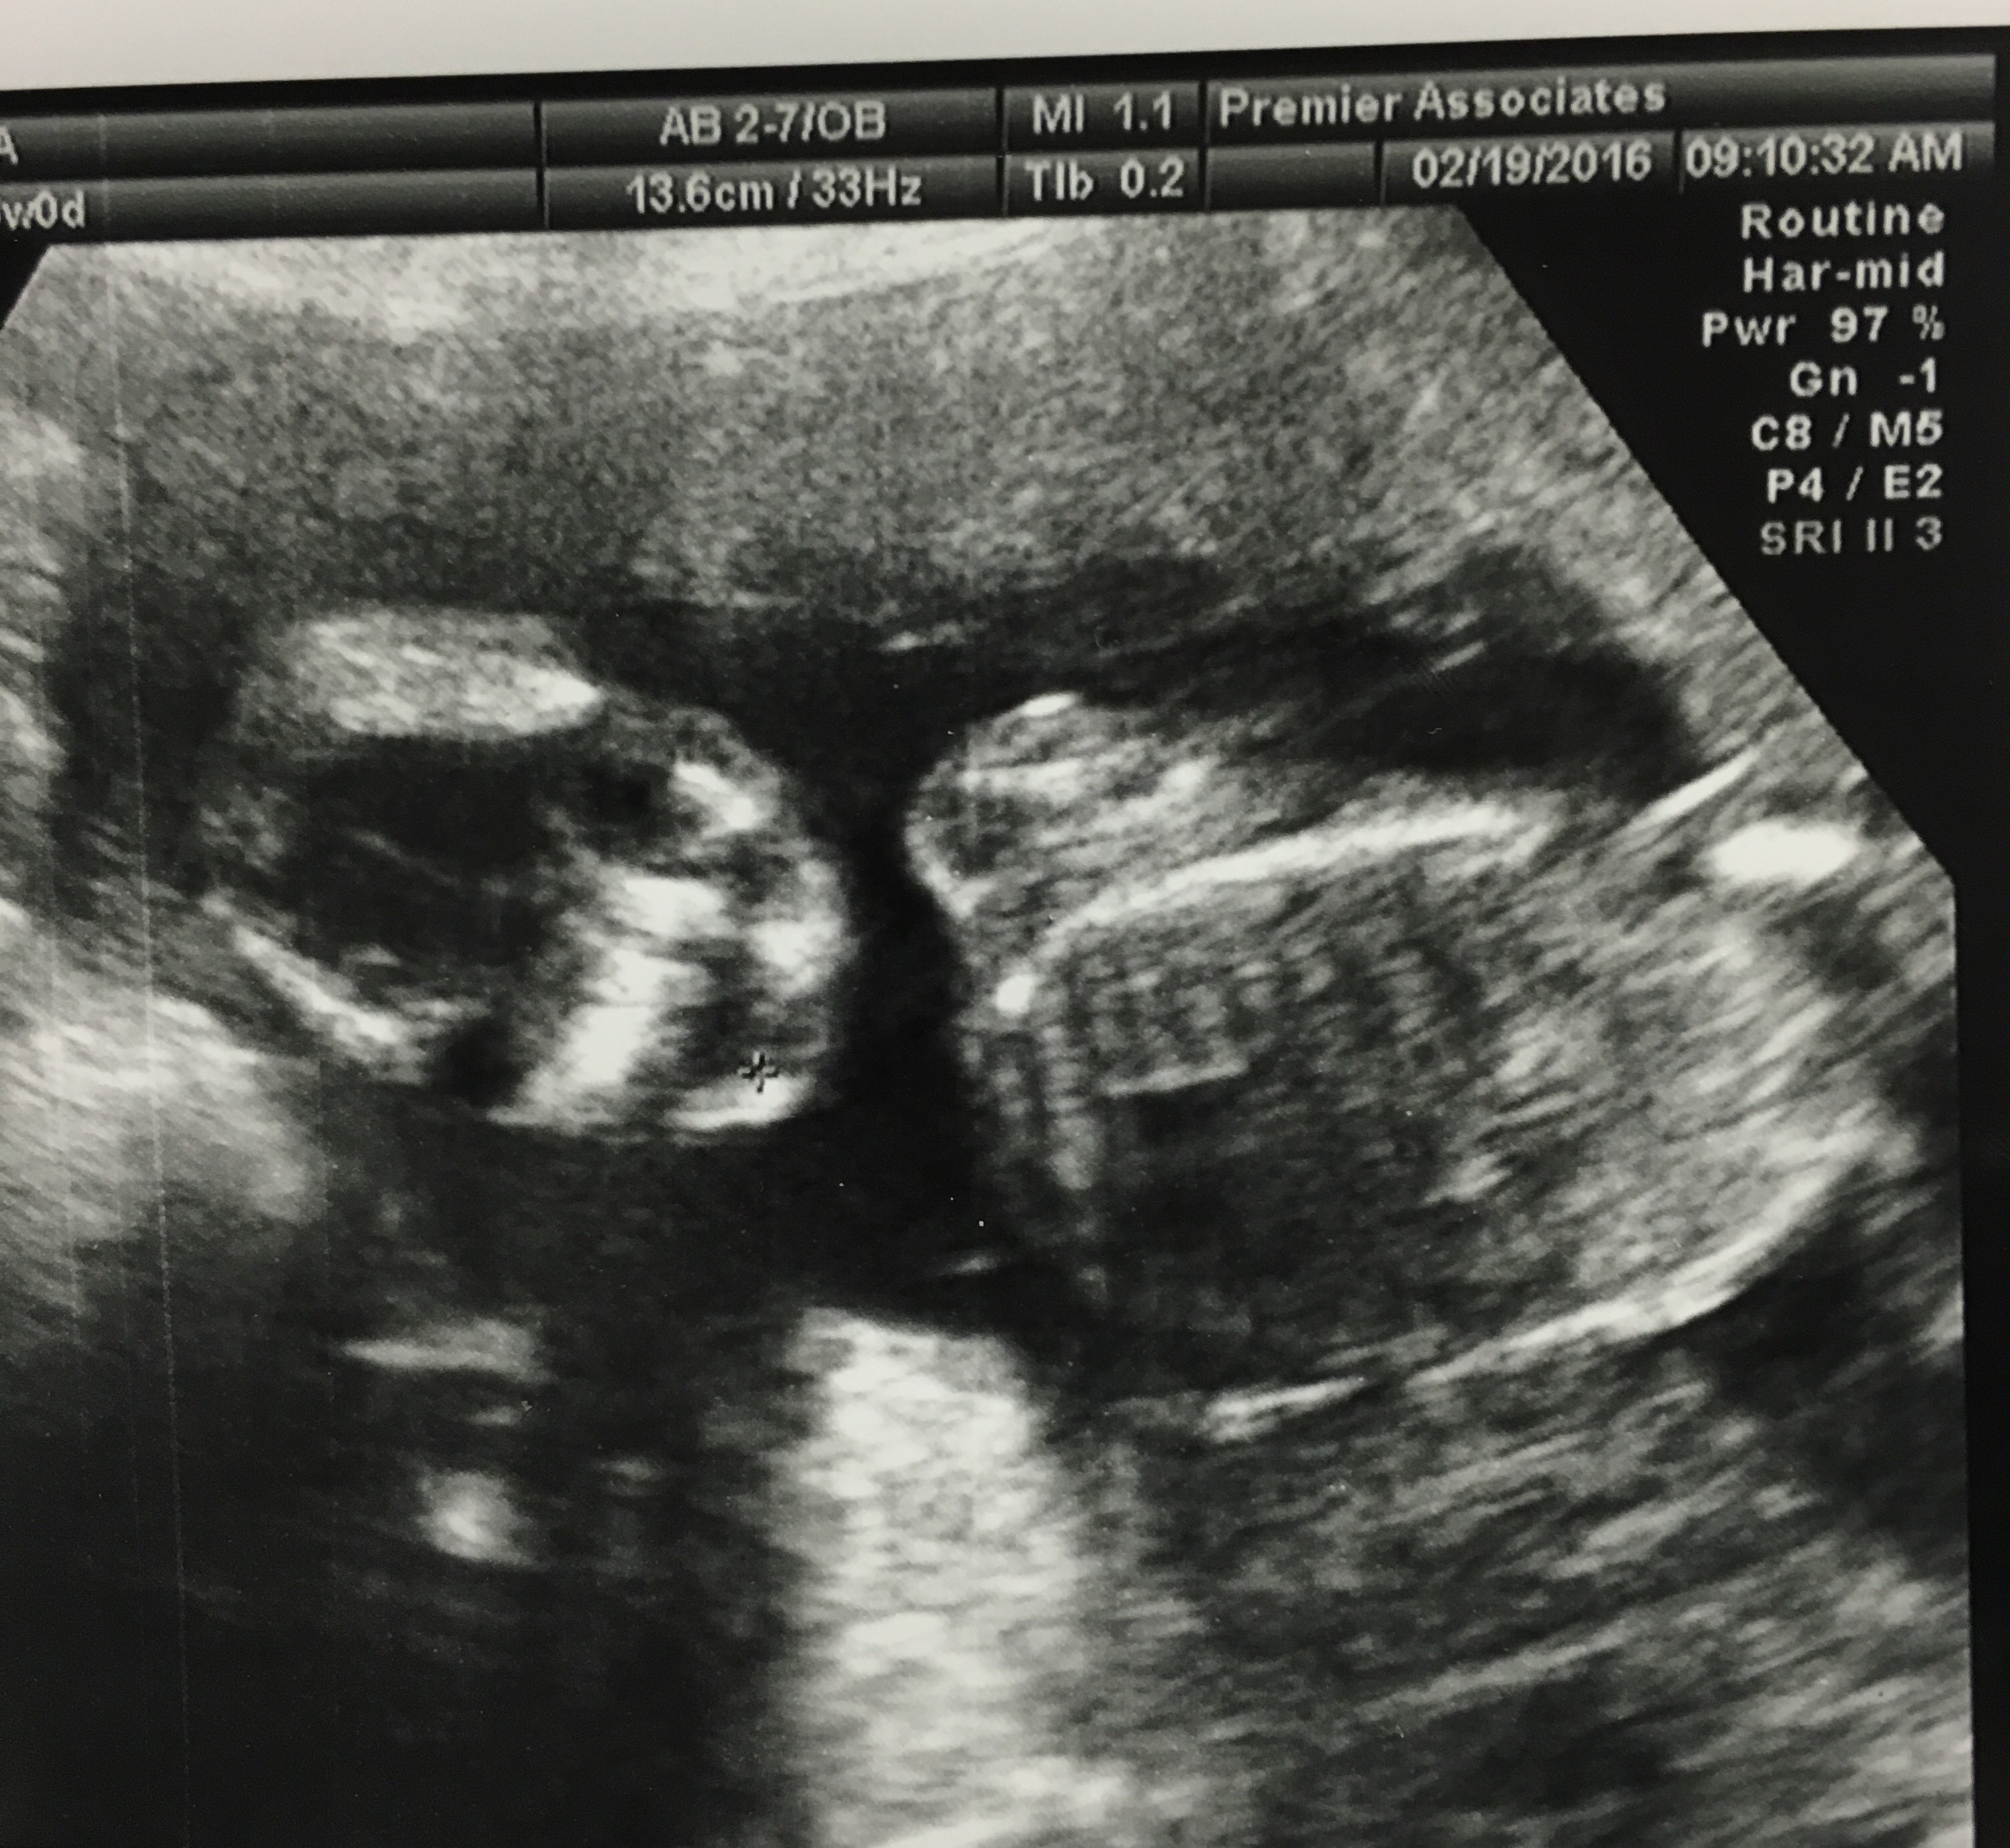

I went to a specialist this week for what I thought was a preeclampsia consultation. I was a little surprised that they wanted to do an ultrasound since I had just had one the week before. This was a Level 2 machine so the ultrasound pictures were very clear.

To me it looks like the baby is smiling and waving hiiii!

I feel like that looks like Gracie’s face.

I was all very excited after this sonogram, texting the pictures to everyone I knew. Then quickly things changed. They sat me down with a genetic counselor to tell me the ultrasound showed a soft marker for Trisonomy 21. It’s called an Echogenic Bowel. Instantly I was crying. My husband stayed home with the kids because we thought this was going to be a very basic appointment so I was all alone.